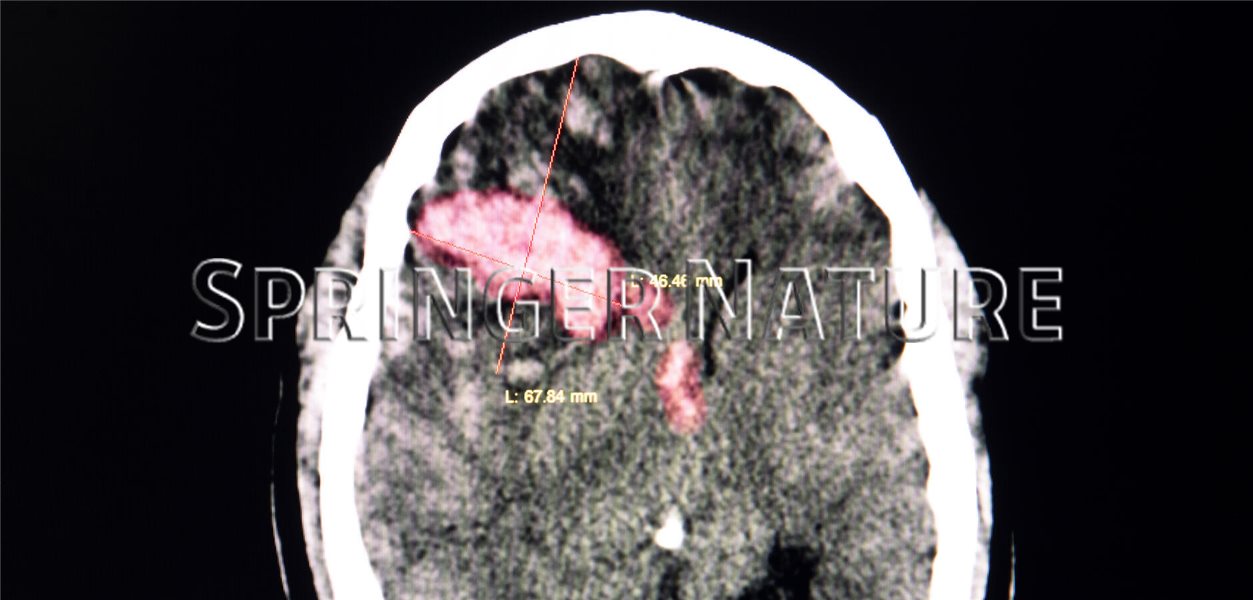

Anzeichen einer Hirnblutung nach einem Sturz oder Schlag Kommt es infolge einer Kopfverletzung zu einer Hirnblutung, sind ein Druckgefühl im Kopf, Probleme bei der Mimik, beim Gehen oder Sprechen, Konzentrationsprobleme, aber teilweise auch Lähmungen oder Krampfanfälle typische Symptome. Nach einem Unfall, Sturz oder Schlag auf den Kopf kann sich im Gehirn ein Bluterguss bilden Chronisch: Die Symptome entwickeln sich allmählich über Wochen, Monate oder Jahre hinweg

Hirnblutung Risikozeit nach Sturz Info Guide. Ältere Menschen haben ein höheres Risiko für verzögerte Blutungen Ein Sturz auf den Kopf kann viele Verletzungen verursachen: von Beule und Gehirnerschütterung bis zum Schädel-Hirn-Trauma oder sogar Hirnblutung

Hirnblutung als Schlaganfall Ursachen, Symptome & Behandlung. Eine Hirnblutung ist eine ernste Komplikation einer Gehirnerschütterung Andere Formen der Hirnblutung nach einem Sturz sind ebenfalls möglich (epidurale Blutung, Subarachnoidalblutung, intrazerebrale Blutung)